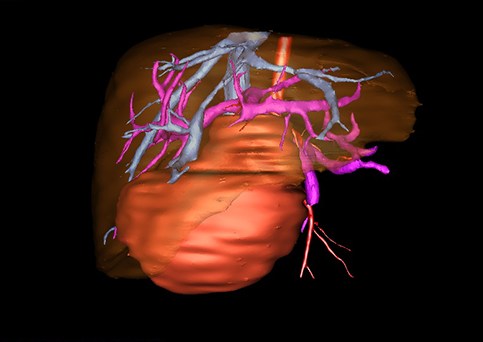

近年来由于数字医学的发展,基于可视化三维重建技术的计算机辅助手术系统极大推进了小儿肝脏肿瘤的精准手术的进步。可以立体透视肝脏解剖、精确掌握肝段的边界、精确测算肝段乃至任意血管所支配的功能体积、准确定位病灶及其与邻近血管的解剖关系,最终对不同手术方案进行比较、筛选和优化。因此,计算机辅助手术规划系统是实现精准肝切除的有力辅助工具,是未来数字外科、精准外科等21世纪外科新理念的重要技术支撑。

计算机辅助手术规划系统具有良好的操作可行性、计算准确性和三维显示效果,可半透明、交互式显示真实的肝内立体解剖关系和空间管道变异,准确计算肝内管道的直径、走行角度,两点间的垂直距离,和任意血管的支配或引流范围等传统二维影像无法获取的信息,有助于实施个体化手术,提高了手术的确定性、预见性和可控性。计算机辅助手术规划系统可直观显示预留肝脏的结构和功能,并可通过虚拟切割功能辅助术者对手术方案进行蹄选和优化,系统评估手术风险和制定对策,改变了部分二维规划的术式和切除范围,使部分二维规划认为不能切除的患者成功手术,提高了手术的根治性、安全性和病变的可切除性,更加符合精准肝脏外科的术前规划要求。详见第11章。

随着计算机技术及影像检查技术的不断发展,以精确的术前影像学和功能评估、精细的手术操作为核心的精准肝切除技术日益受到重视。基于数字医学的计算机辅助手术技术(computer-assisted surgery,CAS)则是实现肝脏精准手术操作的基础。计算机辅助手术系统(CAS)可将术前二维(two dimensional,2D)的CT/MRI影像数据进行三维(three dimensional,3D)重建,建立个体化的肝脏三维解剖模型,清晰显示肝脏内脉管系统的走行及解剖关系,还原病灶与其周围脉管结构的立体解剖构象,准确地对病变进行定位、定性和评估,制定合理、定量的手术方案,实施个体化的肝脏血管取舍分配方案及实施精准肝脏手术。一般认为CAS包括:创建虚拟的患者的图像;患者图像的分析与深度处理;诊断、手术前规划、手术步骤的模拟;术中实时导航。应用本技术后,由于可以更清晰地看出肿瘤的界限,特别是根据肝血管的显影,判断出肿瘤与门静脉及肝静脉的关系以在手术前较准确地估计出手术成功切除的可行性。以往部分根据普通强化CT判断无法手术的病例而被评估为可以成功切除并手术成功。